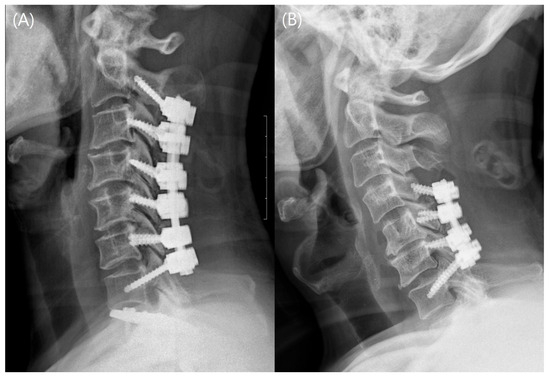

2.2. Surgical Procedures and Postoperative Management

2.3.1. Evaluation of Fusion-Related Complications